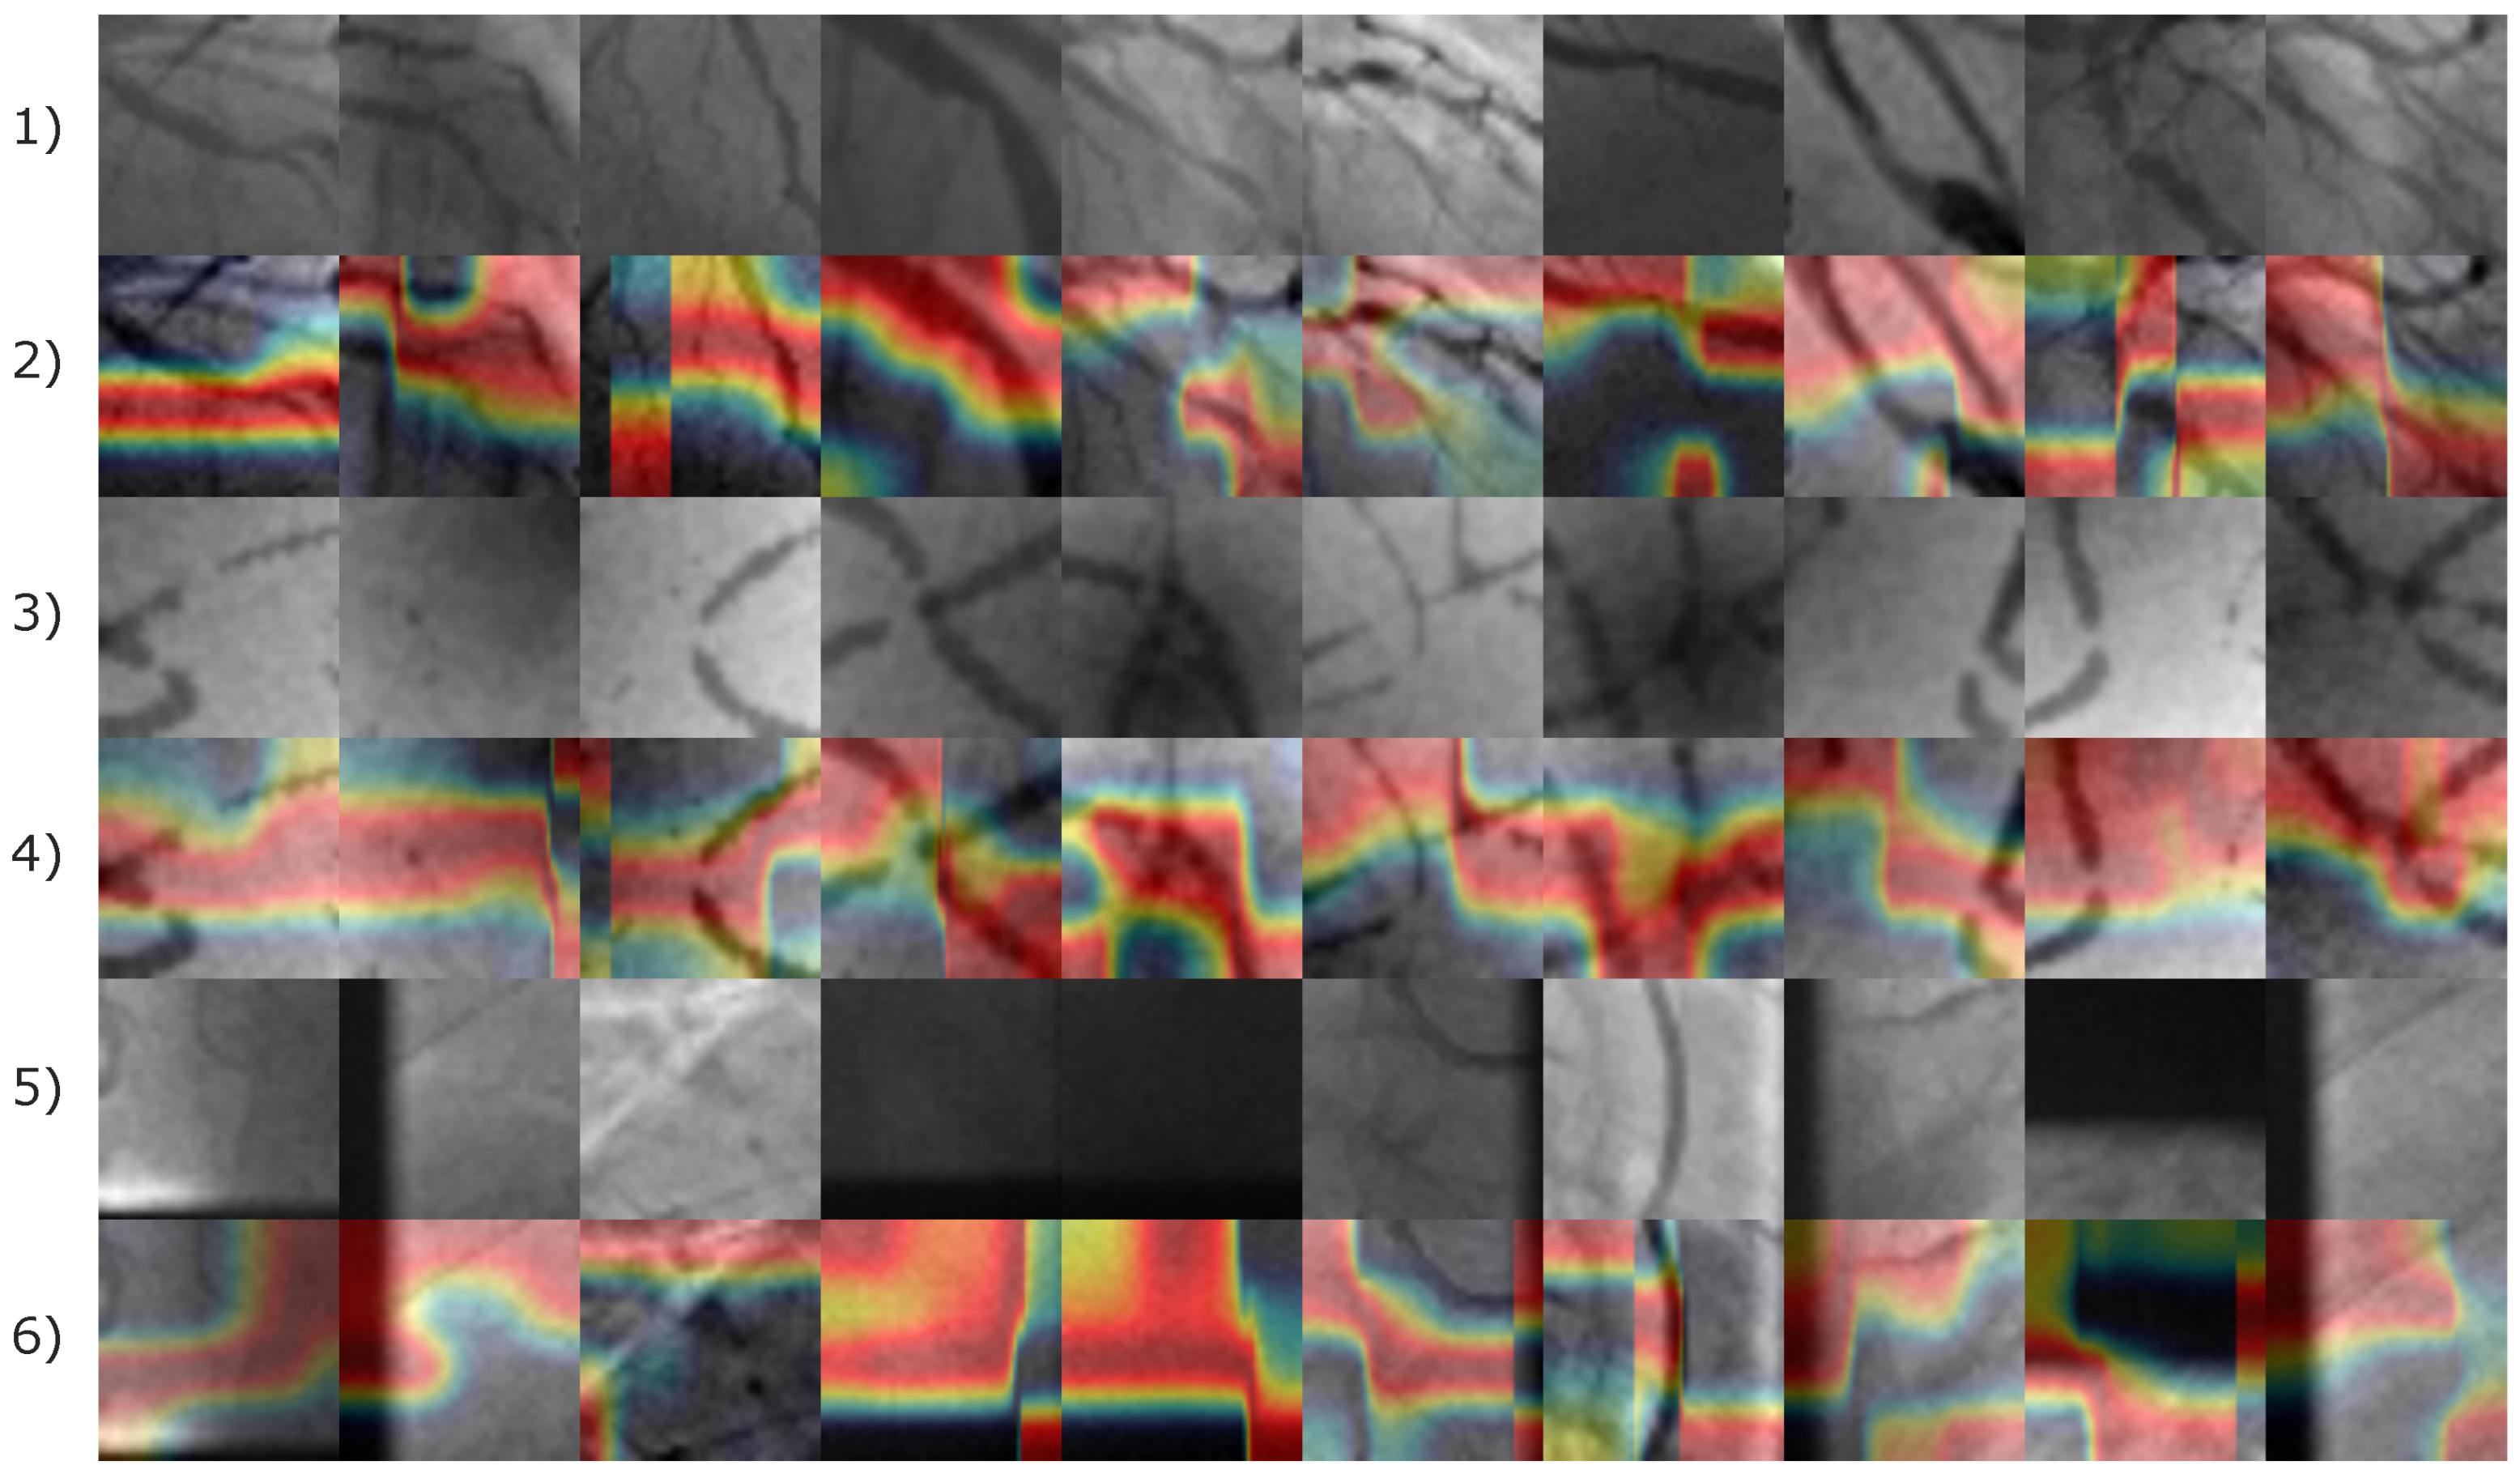

In order to explore details about the image features that allow the proposed CNN model to classify positive and negative coronary stenosis cases, the Grad-CAM technique was used [50]. Figure 13 presents distinct images from the Stenosis608 database, consisting of 21 positive coronary stenosis cases with relevant features marked in a heatmap by the Grad-CAM method.

Figure 13.

Image samples of the Stenosis608 image database. First and third rows illustrates the original images of positive and negative coronary stenosis cases, respectively. The second and fourth rows display the corresponding Grad-CAM heatmaps, where a color gradient from red to blue represents feature importance; red regions highlight the most influential features, while blue denotes areas of minimal contribution to the classification.

According to Figure 13, the image features leading the CNN model to produce a positive classification result are almost related to the pixels corresponding to arteries. Consequently, for negative stenosis classification results, the model involves features from arteries and non-artery pixels. In Figure 14, the corresponding Grad-CAM results from the Antczak image database are also presented.